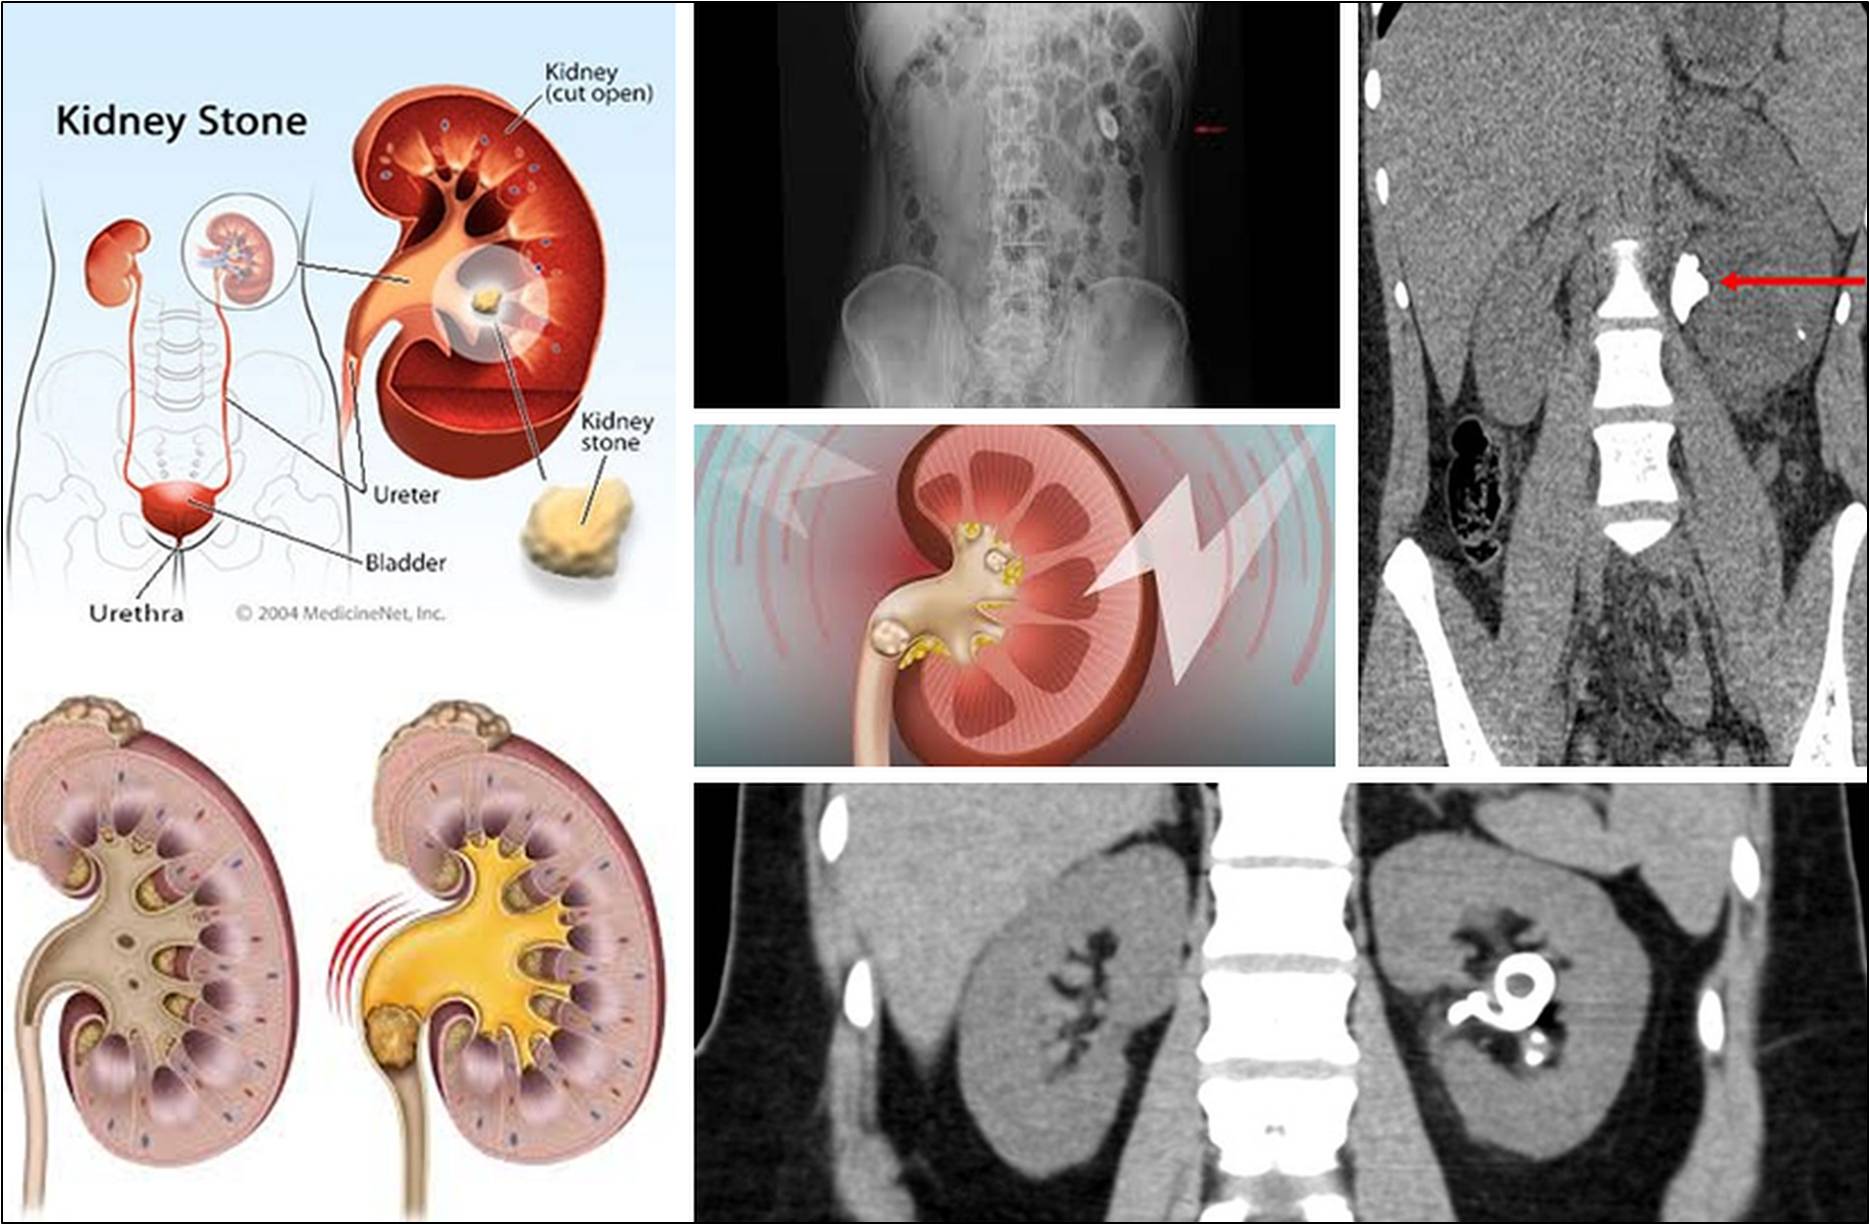

Kidney Stone Treatment (A Urologist's Guide) FeM Surgery